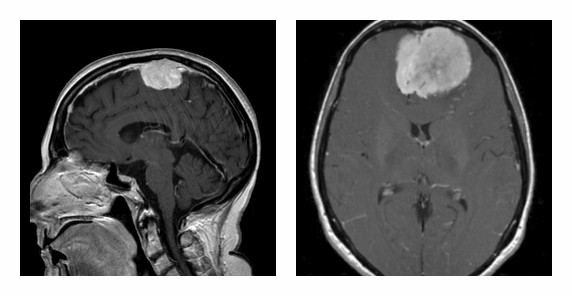

Μηνιγγίωμα Εγκεφάλου

Τα Μηνιγγιώματα του Εγκεφάλου είναι, ως επί το πλείστον, καλοήθεις όγκοι που προέρχονται από την αραχνοειδή μήνιγγα (ένα από τα περιβλήματα του εγκεφάλου) και παρουσιάζουν συνήθως αργό ρυθμό ανάπτυξης. Σε μεγάλο αριθμό ασθενών δεν προκαλούν συμπτώματα, όταν όμως γίνουν συμπτωματικά εκδηλώνονται συνήθως με κεφαλαλγία, αλλά και με άλλα συμπτώματα ανάλογα με την εντόπισή τους (ζάλη, έμετος, μυϊκή αδυναμία σε χέρι ή πόδι, διαταραχές οράσεως, όσφρησης, ακοής ή ομιλίας, ψυχικές/συναισθηματικές διαταραχές, επιληπτικές κρίσεις κ.ά.). Το μηνιγγίωμα διαγιγνώσκεται με απεικονιστικές εξετάσεις όπως αξονική και μαγνητική τομογραφία.

Τα μηνιγγιώματα είναι πιο συχνά σε γυναίκες μέσης ηλικίας (περίπου δύο φορές πιο συχνά από ότι στους άντρες). Στα ασυμπτωματικά μηνιγγιώματα (και κυρίως όταν έχουν μικρό μέγεθος) προτείνεται συνήθως η παρακολούθηση, ενώ σε συμπτωματικά μηνιγγιώματα η ενδεδειγμένη θεραπεία είναι η χειρουργική εξαίρεση. Συνδυαστικά με την χειρουργική αντιμετώπιση ή σε περιπτώσεις που λόγω της εντόπισής τους είναι δυσχερής η χειρουργική εξαίρεση, μπορεί να εφαρμοστεί η μέθοδος της στερεοτακτικής ακτινοχειρουργικής.